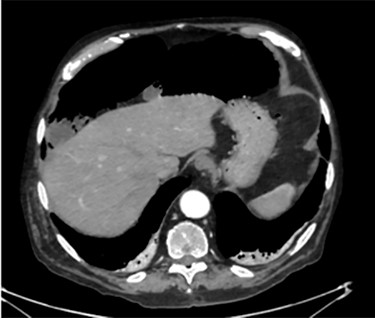

Unfortunately, once he returned home his temperature started to rise up to 38°C and he was readmitted to the hospital. A new contrast-enhanced Chest/Abdomen CT showed a bilateral pneumonia and a massive amount of intraperitoneal free gas, mainly in the abdominal upper quadrants (Fig. 2). No fat stranding, nondilated bowel, no vascular abnormalities and no free fluid were detected. Although the CT showed an evident worsening, the patient still remained completely asymptomatic on physical examination. Accordingly, he started to be treated with meropenem for pneumonia (Escherichia coli was isolated into the sputum) and he finally agreed to underwent diagnostic laparoscopy. Surprisingly, that was definitely not a case of pneumoperitoneum but an idiopathic PCI as we found multiple intramural air content cyst, about 2–3 cm in diameter, all around the small bowel loops and mesentery (Fig. 3). No intra-abdominal maneuvers were made. The patient had an unremarkable recovery (Clavien–Dindo classification grade was 1) [3] and he was discharged home on postoperative Day 15 in well condition, once he had recovered from pneumonia.

A moderate amount of intraperitoneal gas is present anteriorly to the small bowel.